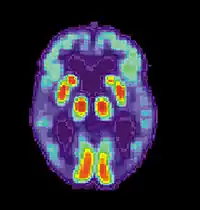

Для того, щоб відрізнити хворобу від інших нозологій і різновидів деменції, використовуються складні методи медичної візуалізації — комп'ютерна томографія, магнітно-резонансна томографія, Однофотонна емісійна комп'ютерна томографія або позитрон-емісійна томографія[76].

Апаратуру SPECT- і PET-візуалізації при її доступності використовують для підтвердження діагнозу спільно з іншими методами оцінки, що включають аналіз ментального статусу[90]. У людей, які вже страждають від деменції, SPECT дозволяє більш ефективно диференціювати хворобу Альцгеймера від інших причин, у порівнянні зі стандартним тестуванням і вивченням анамнезу[91]. Можливість спостерігати відкладення бета-амілоїду в мозку живих людей з'явилася завдяки створенню в Піттсбурзькому університеті Піттсбурзького розчину B, що зв'язується з амілоїдними відкладеннями при введенні в організм. Короткоживучий радіоактивний ізотоп вуглець-11 у поєднанні дозволяє визначати розподіл цієї речовини в організмі і отримувати картину амілоїдних відкладень у мозку хворого за допомогою ПЕТ-сканера[92]. Показано також, що об'єктивним маркером хвороби може бути утримання бета-амілоїду або тау-білка у спинномозковій рідині[93]. Ці два нові методи активували пропозиції про розробку нових діагностичних критеріїв[22][78].